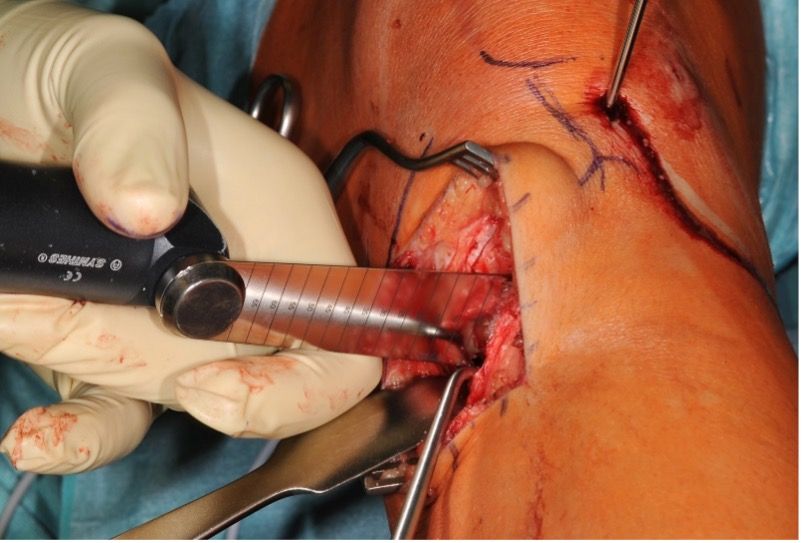

Procedure for (ascending) biplanar osteotomy

Now a blunt Hohmann retractor is placed dorsally directly on the bone, which displaces the critical structures (nerves, vessels and popliteal muscle) to the dorsal side and provides protection during the cutting. The knee is then positioned in 90° flexion. For the osteotomy we use three new and different saw blades. The first part of the osteotomy is performed with a short saw blade with markings (50 mm, 0.9 mm thickness) from medial below the K-wires (up to around 10 mm before the lateral cortex); this should be performed with continuous irrigation for cooling (Fig. 6a).

Thereafter, the anterior cortex is cut with the same saw blade (Fig. 6b). It is important that the dorsolateral cortex is completely divided (we use a second longer saw blade for this). With internal rotation of the tibia this can be presented well under image intensifier control. Due to the triangular form of the tibia the dorsal cut must be longer than the ventral one.

The ascending tuberosity osteotomy is performed with a thinner saw blade (50 mm, 0.7 mm thickness) in 90° flexion with an angle of around 110° to the horizontal and parallel to the ventral tibial edge (Fig. 6c). The thickness of the tuberosity fragment should be 1−2 cm. The tuberosity osteotomy must go through the lateral cortex to facilitate subsequent mobilization.